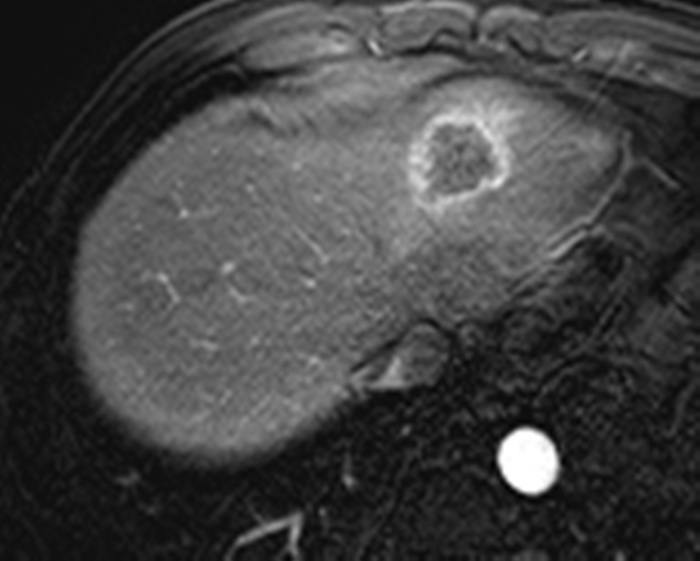

Ung thư đường mật

» Thông tin: Nam giới – 57 tuổi.

» Lâm sàng: Đau bụng.